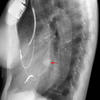

AzyEsop interf

Ex 1